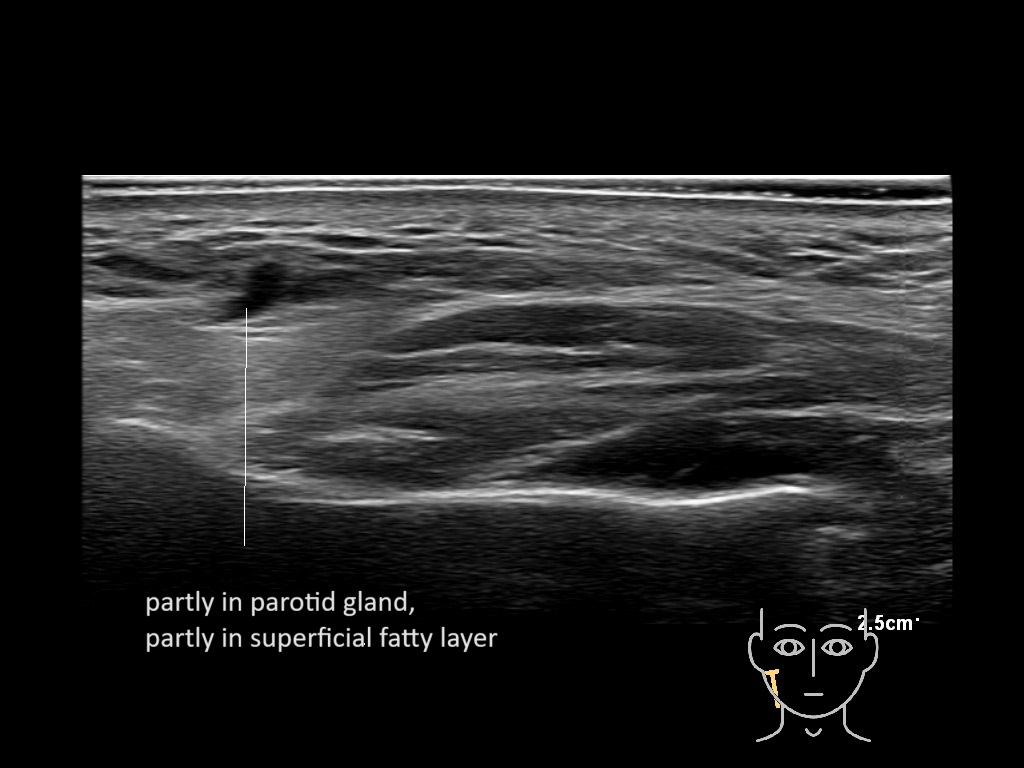

Filler injections in the parotid gland may go unnoticed, however, inflammatory reactions and abscesses may occur. Hypervascularity can be seen with color doppler. Filler deposits are supposed to be injected into the superficial fatty layer . The space to inject into this layer may be limited. Routinely we measure a width of 2-4 millimeters with sometimes subcutaneous layers being less than one millimeter thick.

Study the first image to recognize the different layers. If you are sure about the layers, swipe to the second image to view the answer (if applicable).